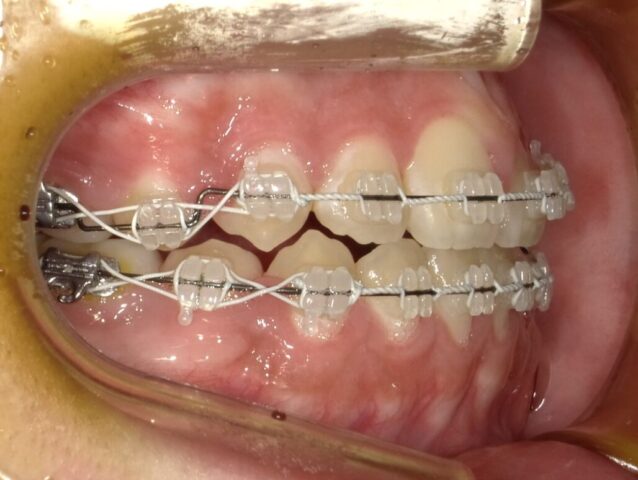

≪右側面観≫

2023年5月

2023年6月